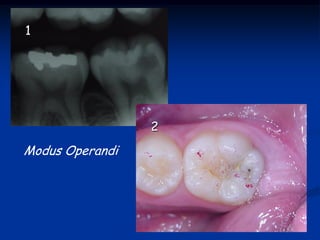

Caso 1- Clínica UNINOVE

1

2

Modus Operandi

TÉCNICA DA MOLDAGEMOCLUSAL É uma técnica restauradora que visa reabilitar o mais próximo ao natural a anatomia oclusal e-ou ocluso-proximal, através da confecção de uma matriz ou moldagem oclusal. Objetivos Minimizar as fases de acabamento Reabilitar a anatomia natural

1 2 Modus Operandi